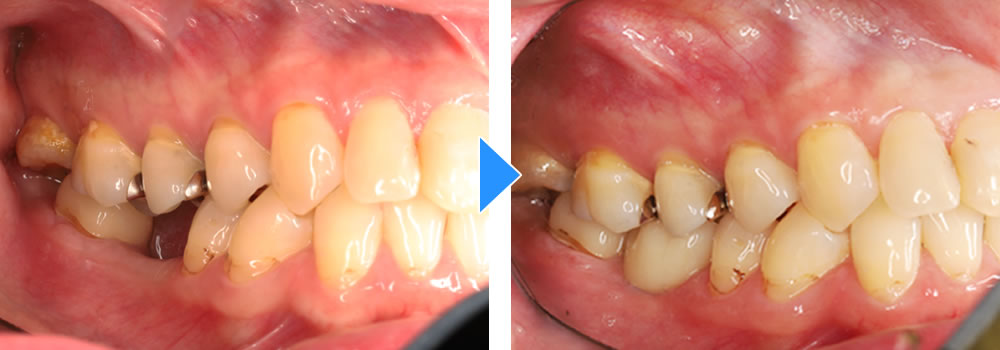

治療前後の比較

治療前後の比較画像です。患者さまにも色合い等大変、満足いただけました。